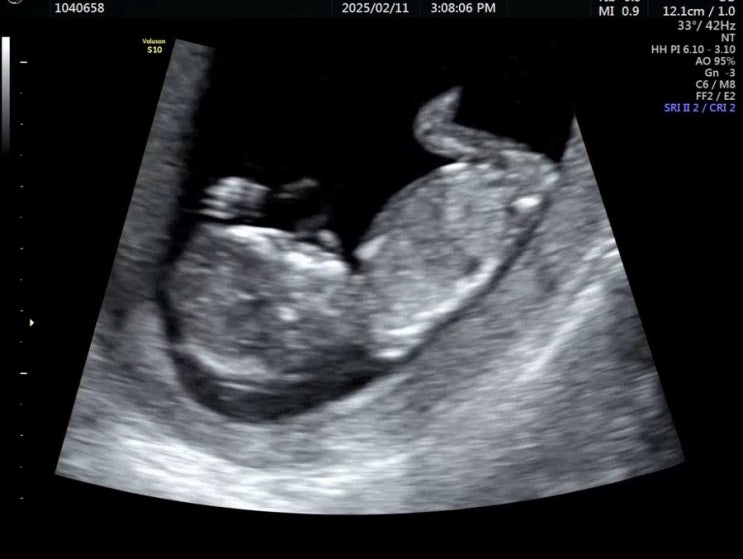

[임신일기] 13. 평화로운 안정기 돌입! - 임신 11주 - 13주

너무너무 평화로워서 블로그 올릴 생각도 못했던 시기 ㅋㅋ 사진만 올려두고 16주인 지금에서야 업데이트를...